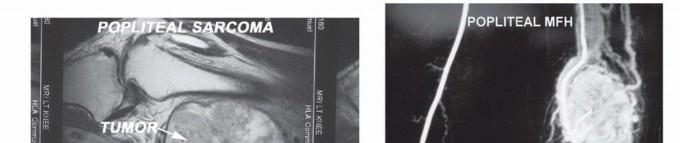

تُعد ساركوما الأنسجة الرخوة في الحفرة المأبضية (المنطقة خلف الركبة) من الأورام النادرة والمعقدة، حيث تمثل أقل من 5% من جميع ساركوما الأنسجة الرخوة في الأطراف. نظرًا لموقعها الحساس والقرب الشديد من الهياكل العصبية الوعائية الرئيسية والمفصل، فإن الجراحة في هذه المنطقة تمثل تحديًا كبيرًا يتطلب دقة جراحية فائقة وخبرة متقدمة. في الماضي، كانت هذه الأورام تُعالج غالبًا بالبتر كحل وحيد لضمان إزالة الورم بشكل كامل، ولكن بفضل الفهم الأعمق لبيولوجيا الورم، والتقدم الهائل في تقنيات التصوير التشخيصي، والتطورات في العلاج الكيميائي والإشعاعي، أصبح بالإمكان الآن إجراء عمليات جراحية تحافظ على الطرف في معظم الحالات، مما يمنح المرضى فرصة للحفاظ على جودة حياتهم ووظيفة أطرافهم.

- ساركوما متعددة الأشكال غير المتمايزة (Undifferentiated Pleomorphic Sarcoma - UPS): كانت تُعرف سابقًا باسم الساركوما الليفية النسيجية الخبيثة (MFH).

- التصوير بالرنين المغناطيسي (MRI): هو الفحص التصويري الأكثر أهمية لأورام الأنسجة الرخوة. يوفر صورًا مفصلة للأنسجة الرخوة، مما يساعد على تحديد حجم الورم بدقة، حدوده، علاقته بالهياكل العصبية والوعائية الرئيسية (مثل الوريد الصافن الكبير والشريان المأبضي والأعصاب)، ومدى تغلغله في العضلات أو العظام.